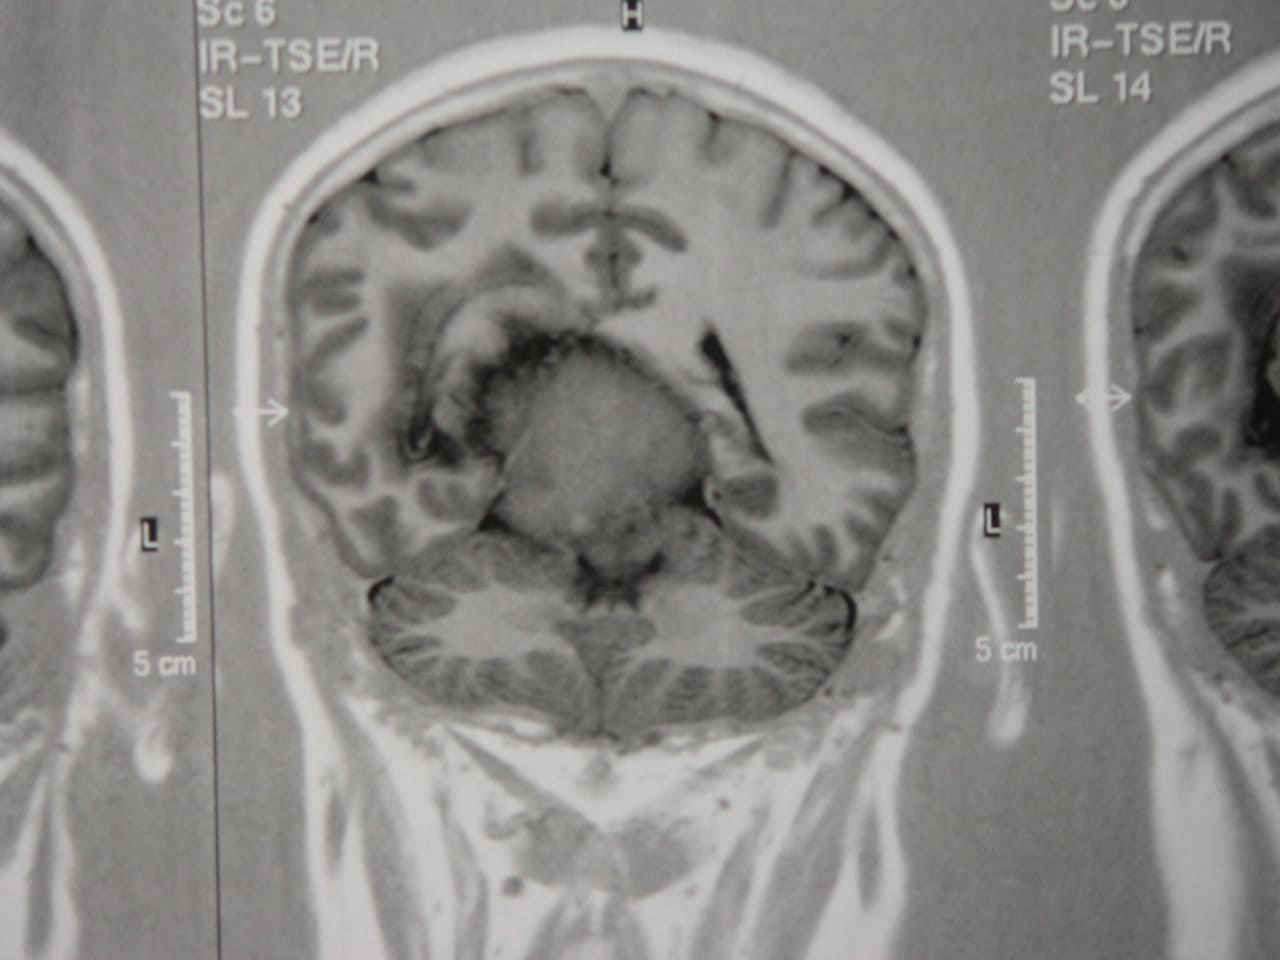

El diagnóstico se puede confirmar y el tumor localizar mediante:

• TAC cerebral

• RM cerebral